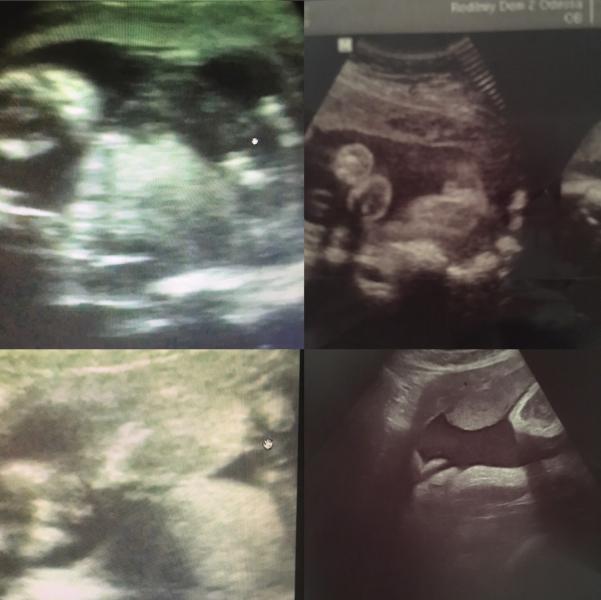

Вот наши фото пола 🙈🙈🙈нам давали только вот маленький или маленькая шкода сохраняет интригу !!! Сказала врач должна родить очень скоро , отпишусь кто в итоге 🙈

@miss_alena22, спасибо большое 😍😍😍что то у нас вообще не понятно что 🙈

а там пол не видно)))) на узи их только по телику показуют(пол) а на фото не видно...)))